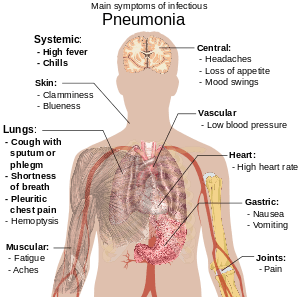

Pneumonia is an inflammatory condition of the lung affecting primarily the microscopic air sacs known as alveoli.[2][3] Typical signs and symptoms include a varying severity and combination of productive or dry cough, chest pain, fever, and trouble breathing, depending on the underlying cause.[4]

People with infectious pneumonia often have a productive cough, fever accompanied by shaking chills, shortness of breath, sharp or stabbing chest pain during deep breaths, and an increased rate of breathing.[18] In the elderly, confusion may be the most prominent sign.[18]

The typical signs and symptoms in children under five are fever, cough, and fast or difficult breathing.[19] Fever is not very specific, as it occurs in many other common illnesses, may be absent in those with severe disease, malnutrition or in the elderly. In addition, a cough is frequently absent in children less than 2 months old.[19] More severe signs and symptoms in children may include blue-tinged skin, unwillingness to drink, convulsions, ongoing vomiting, extremes of temperature, or a decreased level of consciousness.[19][20]

Bacterial and viral cases of pneumonia usually present with similar symptoms.[21] Some causes are associated with classic, but non-specific, clinical characteristics. Pneumonia caused by Legionella may occur with abdominal pain, diarrhea, or confusion,[22] while pneumonia caused by Streptococcus pneumoniae is associated with rusty colored sputum,[23] and pneumonia caused by Klebsiella may have bloody sputum often described as "currant jelly".[17] Bloody sputum (known as hemoptysis) may also occur with tuberculosis, Gram-negative pneumonia, and lung abscesses as well as more commonly with acute bronchitis.[20] Mycoplasma pneumonia may occur in association with swelling of the lymph nodes in the neck, joint pain, or a middle ear infection.[20] Viral pneumonia presents more commonly with wheezing than does bacterial pneumonia.[21] Pneumonia was historically divided into "typical" and "atypical" based on the belief that the presentation predicted the underlying cause.[24] However, evidence has not supported this distinction, thus it is no longer emphasized.[24]

Physical exam